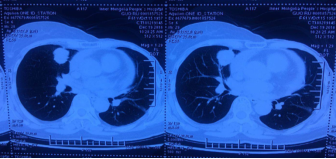

根据2018版CSCO BC指南及PALOMA3研究数据,患者二线治疗:哌柏西利+氟维司群,具体用法:氟维司群:500mg,im,d1、14、28,之后每28 d一次。哌柏西利:125mg起始,3周休1周。前两周期d1、d15、d21d定期复查血象。

疗效评价:PR。转移灶大小:22×24mm